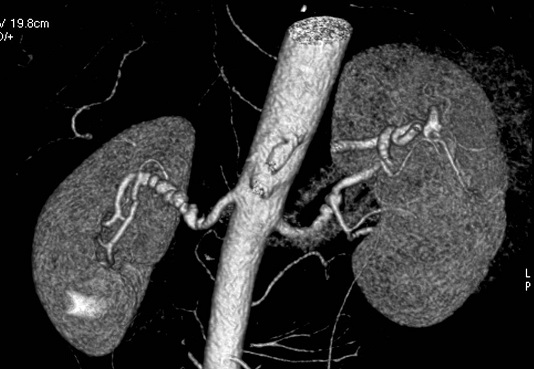

Image Diagnosis

A picture is worth a thousand words, and in the fields of medicine and product development, non-intrusive diagnostic images such as X-rays, CT scans, and MRIs can be the difference between life and death. Our team has supported numerous medical professionals and industrial experts in resolving critical issues, aiding both human patients and products alike.

We work with a large group of medical professionals to analyze and curate medical images, including ultrasound, x-ray CT, and MRI.